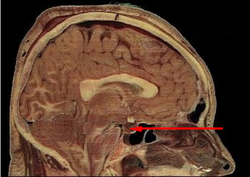

Hipofiza se nalazi s donje strane mozga

Hipofiza je na dnu mozga. Štite ju koštana struktura zvana sella turcica (tursko sedlo) sfenoidne kosti i ne daje joj mnogo mjesta za se proširiti.[1] Henry Vandyke Carter - Henry Gray (1918): Anatomy of the Human Body. Bartleby.com: Gray's Anatomy, Plate 1180

Smještaj

Prema svom položaju najzaštićeniji je dio tijela. Velika je oko 1 cm i teška oko 0,5 grama. Smještena je na bazi velikog mozga, kao moždani privjesak koji visi na turskom sedlu. Djeluje na rast tijela, krvni tlak, rad bubrega, promet tvari. Hipofiza usklađuje rad drugih žlijezda s unutarnjim lučenjem. Također je zovu i glavnom ili centralnom žlijezdom.